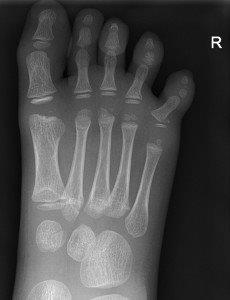

Undisplaced metatarsal fractures

Minimally displaced oblique of the 5th metatarsal

Fractures of distal 2nd-4th metatarsals

- CAM boot weight bearing as tolerated with Fracture Clinic follow up in 1 week.1